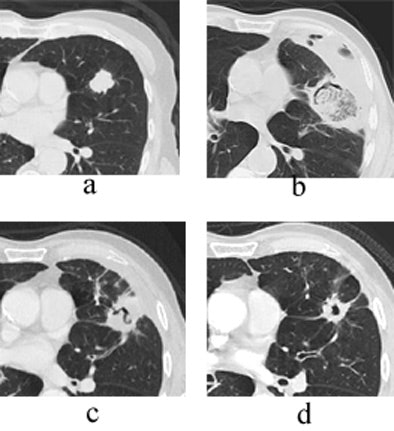

| Transverse thin-section CT of a lingular segment nodule prior to RFA and one, three, and six months after RFA. (a) Baseline scan obtained prior to RFA shows a 2.2 x 2.8-cm nodule. (b) Scan one month after RFA shows marked interval increase in nodule size with early formation of a thick-walled cavity and adjacent anterolateral complicated hydropneumothorax. (c) Scan three months after RFA demonstrates interval regression of cavitary lesion and resolving adjacent hydropneumothorax. (d) Scan six months after RFA shows further interval regression of cavitary lesion and resolved hydropneumothorax. Images courtesy of Drs. Robert Suh, Jonathan Goldin, and Amanda Wallace, UCLA School of Medicine, Los Angeles. |